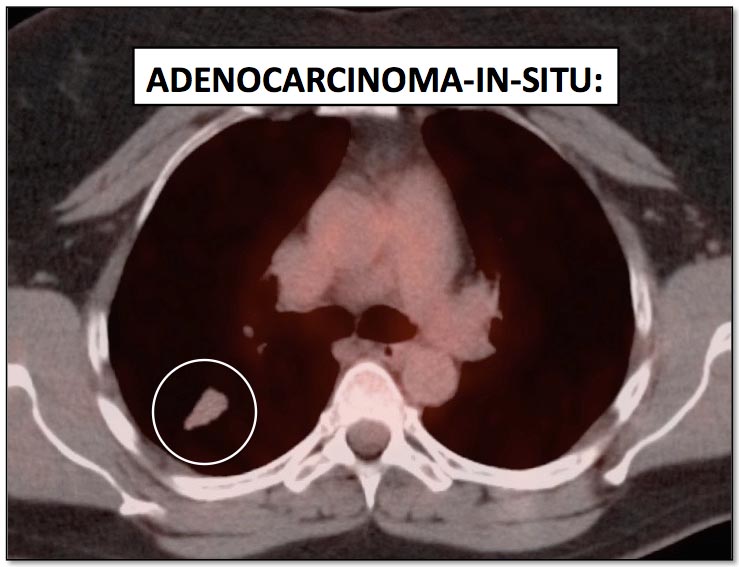

While PET/CT is sensitive for detecting most cancers, there are some malignancies which sometimes demonstrate poor avidity for 18F-FDG, including: [Fig. 1]

- Adenocarcinoma-in-situ (formerly “bronchoalveolar carcinoma”)

Please note that while the above cancers sometimes demonstrate poor metabolic activity, they can also be quite FDG-avid. [Fig. 2]